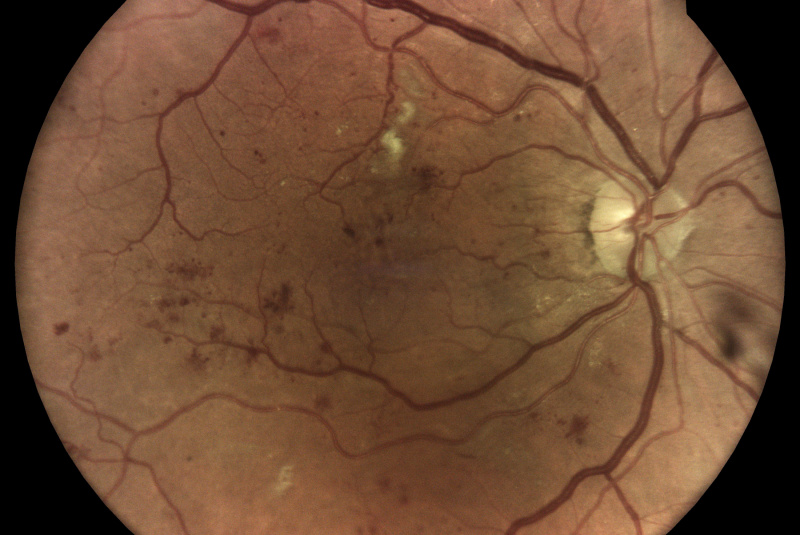

Oproti běžným fundus kamerám je tu využitá patentovaná technológia iCare DRS Plus Confocal Technology. Znížená intenzita záblesku má šetrnejší účinok na zrenicu. Prostredníctvom tohto nemydriatického zariadenia je možnosť vidieť jemné štruktúry sietnice a cievneho systému aj skrz velikost zrenice od 2,5 mm.

Fundus kamera iCare DRSplus urobí celkovo 4 vysoko kvalitné snímky (dve z pravého a dve z ľavého oka), ktoré sa automaticky ukladajú na cloud a posielajú sa na spracovanie AI - umelej inteligencii. Report je dostupný ihneď a ten je možné prekonzultovať s pacientom počas tej istej návštevy u lekára.

- infračervené mapy zvýrazňujúce svetlé a červené lézie/poškodenia

Diabetická retinopatia

Diabetická retinopatia je hlavnou príčinou straty zraku u dospelých vo veku medzi 20 - 74 rokov. Viac ako jedna tretina z odhadovaných 285 mil. ľudí s cukrovkou na celom svete vykazuje príznaky diabetickej retinopatie. Diabetická retinopatia je na vzostupe v dôsledku zvyšujúcej sa prevalancie cukrovky, stárnutia populácie a predlžujúcej sa dĺžky života ľudí s cukrovkou.